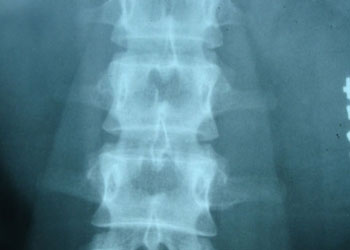

强直性脊柱炎早期诊断有一定困难,但早期诊断及治疗是降低本病病残率的关键。本病多始于青少年。男性多见,起病缓慢,病变多始发于骶髂关节,除腰痛外,可伴有背胸部、颈部僵硬痛及下肢关节肿痛,病变部位长时间休息后僵硬感,活动后减轻或消失。腰椎间盘突...[详细] 2015-11-06

强直性脊柱炎发病年龄越小症状越重,所以青少年时期的发病的危害更大一些。21日,贵阳风湿中医院专家王怀庆教授介绍了强制性脊柱炎的相关知识。他指出,强直性脊柱炎致残率高,一定要引起重视。 据王怀庆介绍,强直性脊柱炎的发病高峰是16-30岁,尤其是青春...[详细] 2015-11-03